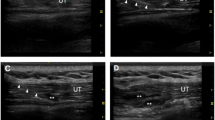

a Immunofluorescence staining showed an increase in the lumen sizes of the penile dorsal artery after lotusine treatment, and quantitation of the diameters is presented in panel b. SMA (red), smooth muscle actin, a specific marker of smooth muscle; MYPT1 (green) (Panel b: Mypt1+ /+, n = 4; Mypt1+ /ΔSM, n = 4; Mypt1ΔSM /ΔSM, n = 3). c, Quantitation of penis weights in the different groups of mice (non-Lot1: Mypt1+ /+, n = 8; Mypt1+ /ΔSM, n = 7; Mypt1ΔSM /ΔSM, n = 5; Lot1: Mypt1+ /+, n = 5; Mypt1+ /ΔSM, n = 5; Mypt1ΔSM /ΔSM, n = 5). d–g, MYPT1-deficient mice showed decreased ICP responses to EFS of the cavernous nerve. d and e, Representative tracings of ICP responses in Mypt1+/+, Mypt1+/ΔSM, and Mypt1ΔSM /ΔSM mice without (d) or with lotusine treatment (e). f Quantification of ICP/MAP in the different groups of mice (non-Lot1: Mypt1+/+, n = 10; Mypt1+/ΔSM, n = 12; Mypt1ΔSM/ΔSM, n = 11; Lot1: Mypt1+/+, n = 10; Mypt1+/ΔSM, n = 10; Mypt1ΔSM/ΔSM, n = 8). The groups of Lot1 were injected by Lot1 (5 mg/kg body weight) once a day and continued for 28 days. The bars indicate the mean values ± SEM; **p < 0.001; ***p < 0.001; t-test.

As Mypt1+/ΔSM mice showed a moderate ED phenotype (ICP/MAP = 0.34 ± 0.03) (Fig. 1a), we used these mice as an ED disease model, although the penile function was not impaired enough to affect fertility. We treated these mice and their littermates with Lot1 via consecutive i.p. injections. The Lot1-treated Mypt1+/ΔSM and Mypt1ΔSM/ΔSM penises showed sizes comparable to those of Mypt1+/+ penises (Fig. 6c). Surprisingly, the lumen diameter of the Mypt1+/ΔSM and Mypt1ΔSM/ΔSM dorsal artery and CC was also restored significantly (Fig. 6a-b, Supplementary Fig. 10). We then measured the penile ICP/MAP in response to stimulation. Upon stimulation with 5 V/12 Hz, control penises treated with Lot1 displayed a 110% increase in the ICP/MAP across the untreated group, but the difference was not statistically significant (p = 0.65) (Fig. 6d, e and f). However, Mypt1+/ΔSM penises showed a significant increase of ICP/MAP after Lot1 treatment (treatment: 0.54 ± 0.02 vs no treatment: 0.39 ± 0.02, p < 0.001), comparable to the effect in Mypt1ΔSM/ΔSM mice (p > 0.05) (Fig. 6d, e and f). Collectively, these observations showed that treatment with Lot1 significantly restored penile function through the upregulation of MYPT1. As Lot1 treatment did not restore penile function in Mypt1ΔSM/ΔSM mice, in which both Mypt1 alleles had been deleted, the efficacy of Lot1 treatment was primarily mediated by targeting MYPT1.